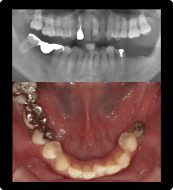

骨造成(サイナスリフト)を伴うインプラント治療

上の奥歯に歯を入れたい

BEFORE/AFTER

症例概要

年代・性別

50歳代 女性

主訴

治療内容

右上6番インプラント治療、サイナスリフト

治療期間

4ヶ月

治療のリスク

インプラント周囲炎のリスクがあるため、メンテナンスに来ていただきます。

治療費用

572,000円(税込)